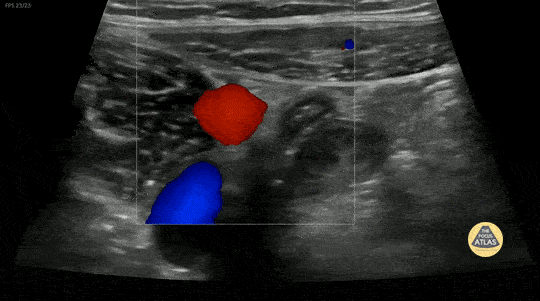

10 y/o with abdominal pain. Normal appendix identified medial to the iliac vessels. Contributor: Elena Chen, MD